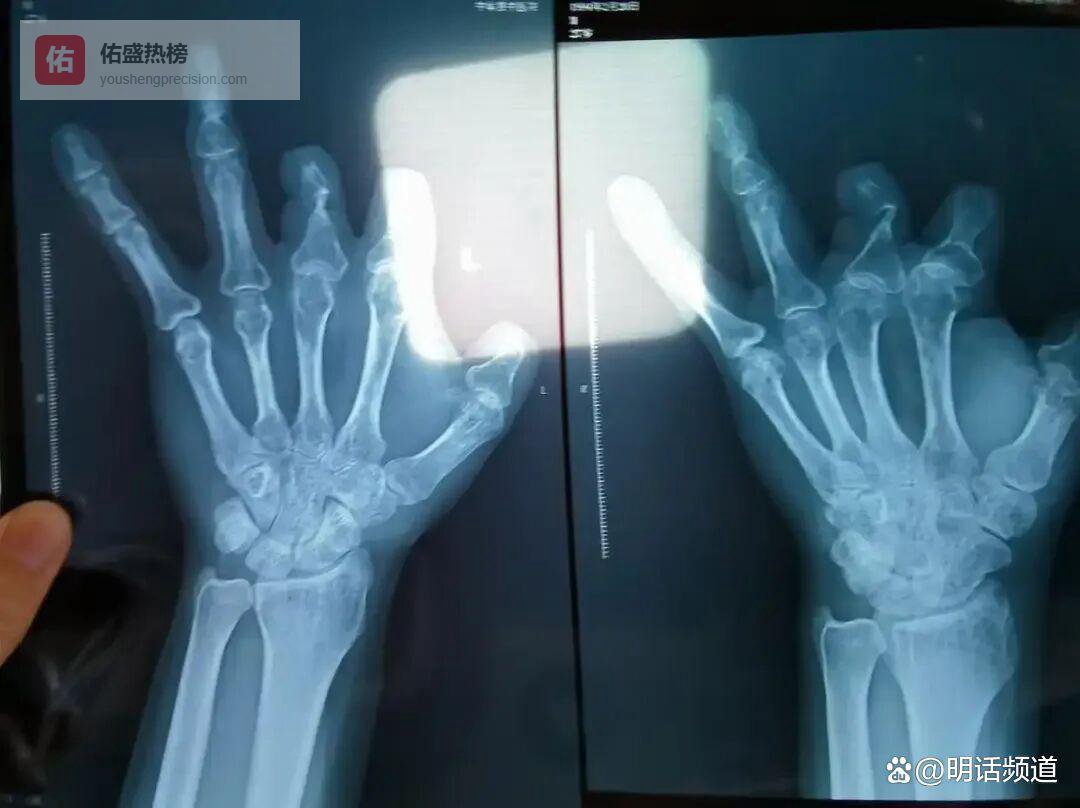

郑大一附院影像科的老陈最近总盯着X光片发呆——那些断指患者的片子上,本该清晰显影的环形吻合装置像凭空消失了。不锈钢材质在X光下会呈现特有亮影,可这些患者体内只有缝合线的痕迹。他偷偷记下异常病例编号,发现主刀医生全是王福建。当第七个患者来取报告时,老陈终于忍不住提醒:“你血管旁边可能缝了东西,去拍个CT看看吧。”

老陈的发现撕开了黑幕。警方后来证实,王福建四年间对94名患者虚假收费205万,把本应植入血管的1.68万元器械扔垃圾桶,甚至缝进患者肌肉里伪造痕迹。那些X光片上的空白,成了94个家庭被欺骗的无声证据。如今老陈总对年轻医生说:“咱们看的是片子,更是良心。”此案直到2021年媒体曝光,王福建才停职,最终于2025年12月因诈骗罪、非国家工作人员受贿罪获刑12年并罚款40万元。